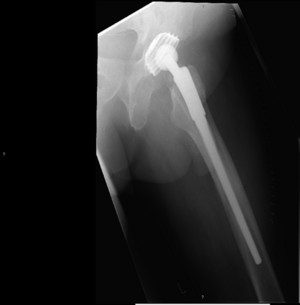

Beim Hüftgelenkersatz verwenden wir unterschiedliche Implantate inklusive der Kurzschaftprothese. Vorzugsweise werden diese, in Abhängigkeit der Knochenqualität, zementfrei eingebracht. Gelegentlich werden teilzementierte Prothesen, sehr selten vollzementierte Komponenten verwendet.

Röntgenaufnahme einer Hüftendoprothese, deutlich sichtbar im rechten Hüftbereich.

Kurzschafttotalendoprothese Hüfte